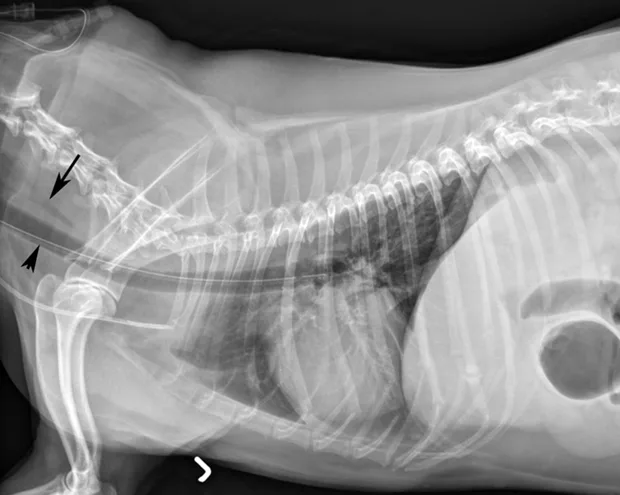

If the tube is in the trachea, the portion running in the proximal cervical region will be visibly ventral to the esophagus on radiography (C).

Replacement of a blocked esophagostomy tube attempted with an awake patient resulted in collapse of the stoma, inadvertent placement of the tube (arrow) into the mediastinum, and subsequent mild pneumothorax.